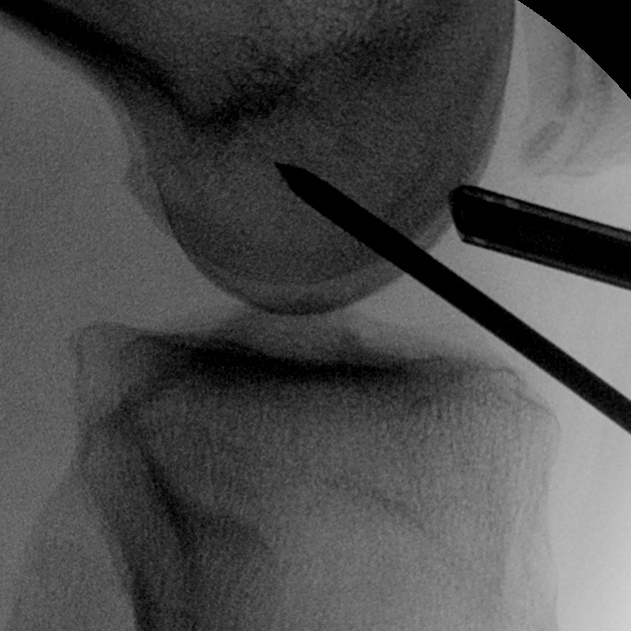

Femoral entry point

- place beath pin just medial to patella tendon

- insert into femoral insertion of ACL on LFC

- check entry on lateral

- imagine posterior femoral condyle as circle

- entry point in centre, but 60% of distance posterior

- drive out lateral femur as standard

- pull pin back through femur so that guide wire passes up into femur

- distal pin now in joint

Tibial entry point

- extend knee

- aim pin for standard origin of ACL

- drive through tibia